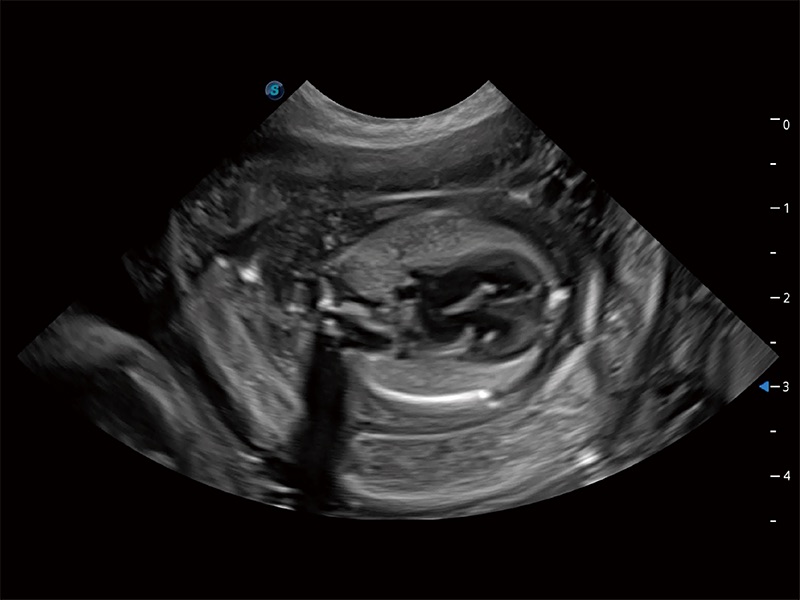

动物是人类最亲密的朋友和最值得信赖的伙伴。亚星官网也一直致力于探索动物专用的超声影像解决方案。全新推出的ProPet系列,是亚星官网在动物超声影像智能化、专业化、精准化的一次跨越式革新。动物不能用言语来表述自己的不适,通过超声影像,ProPet系列搭建了动物医生与不同物种沟通的“桥梁”,为动物医生注入了“治愈之力”。 ProPet 80 是亚星官网匠心打造的一款高端动物专用彩超,采用性能卓越的全新硬件架构,极大提升超声系统的运行效率和数据处理能力,帮助动物医生从容应对日益增多的挑战性病例和日益多样化的临床需求。

高性能和先进的临床应用工具可以为动物医生提供临床信心。ProPet 80 搭载了先进的腹部和浅表应用工具,帮助医生在日常临床实践中发挥前所未有的作用。

ProPet 80 全新的动物超声智能软件和丰富的探头群,为动物医生提供了高清晰度和精细分辨率的图像,无论在宠物、马科、畜牧还是实验室动物等应用中都可以轻松应对,为您的日常工作带来满意的体验。